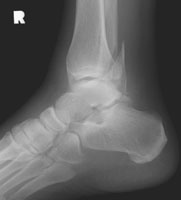

Weber B Fracture

The Weber classification is used to determine the severity of tibiofibular ligament injury by the level of fibular fracture. The Weber B fracture consists of a fracture of the fibula near the joint and a transverse fracture of the medial malleolus (or disruption of the deltoid ligament). This results in partial disruption of the tibiofibular ligament complex and is from supination-lateral rotation injury.

- Click on the image for a larger versionALateral radiograph of the ankle. There is a fibular fracture, near the level of the tibiotalar joint.